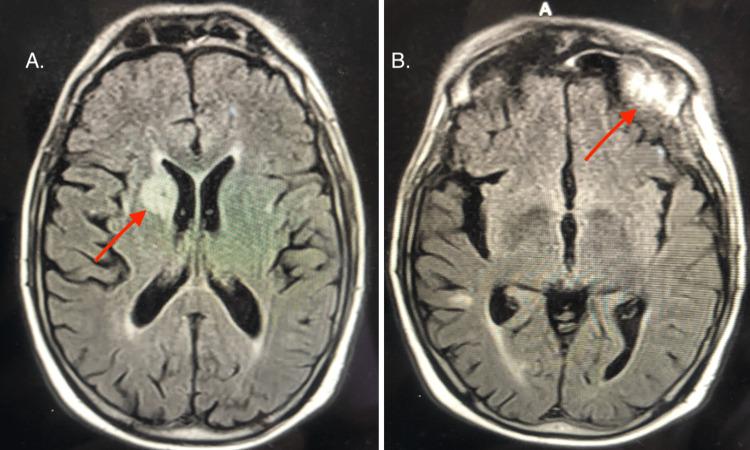

Leptomeningeal carcinomatosis (LC) is a rare complication of malignant tumors that involves metastasis to the meninges surrounding the brain and/or spinal cord. The incidence of LC appears to be increasing, which has been attributed to increased survival times of cancer patients and increased diagnostic sensitivity. In this case, we discuss a patient with a history of colon cancer and lung cancer who was admitted with multiple cranial nerve palsies and sensory deficits. An MRI with contrast showed multiple enhancing intracranial lesions with leptomeningeal enhancement. Neurology and neurosurgery were consulted, and the patient was ultimately discharged to hospice.

软脑膜癌病(LC)是恶性肿瘤的一种罕见并发症,涉及转移至脑和/或脊髓周围的脑膜。LC的发病率似乎在上升,这归因于癌症患者生存时间的延长和诊断敏感性的提高。在本病例中,我们讨论一名有结肠癌和肺癌病史的患者,该患者因多发性颅神经麻痹和感觉障碍入院。增强MRI显示颅内有多个强化病灶伴软脑膜强化。咨询了神经科和神经外科,该患者最终出院接受临终关怀。